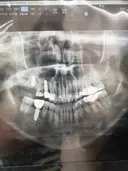

상담원분이 친절하시고 너무 좋았어요! 임플란트 어디서 해야하나 많이 고민했는데 가격도 저렴하니 좋더라구요~ 엘베가 느린건지 타는 사람인지 많은건지 모르겠지만 병원 들어갈때 오래 걸리는 느낌이라 더 긴장되고ㅜㅜ 임플란트가 처음이라 너무 걱정됐는데 괜한 걱정했네요🤭 원장님이랑 간호사분들 너무 친절하셨어요! 과잉진료 이런것도 전혀 없으시구 꼼꼼하니 잘된것 같아서 만족합니다❤️🔥